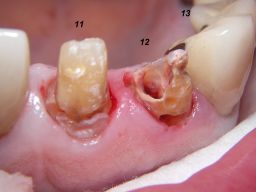

Weil auch die anderen Schneidezahnkronen (12-22) durch Randreparaturen und den schlechten Randschluß erneuerungsbedürftig aussahen, wurden 4 Einzelkronen geplant. Vorher hieß es aber noch, die schlechte Wurzelfüllung im Zahn 12 (Röntgenbild links) besser zu machen. Hierfür wurden am 17.2.06 die alten Kronen 11 und 12 entfernt. Rechts das Bild nach Entfernung von alten Füllungen und Karies.

Links nach Wurzelfüllung beim Einpassen des Titanstiftes. Rechts dann der schon provisorisch beschliffene Amalgamaufbau im Zahn 12.